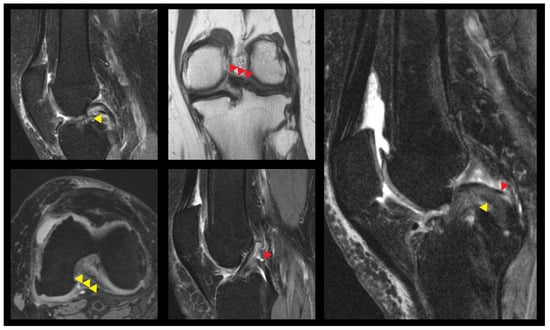

2.1. Image Evaluation